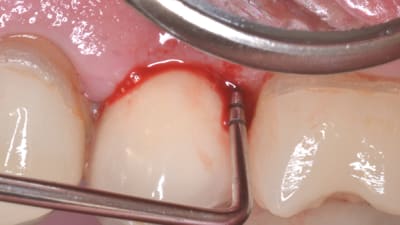

Case Reports Periodontics Implantology Treatment of Peri-implantitis Using a Combined Decontaminative and Regenerative Protocol: Case Report By Nicola Alberto Valente, DDS, Sebastiano Andreana, DDS February 01, 2018 11 min read